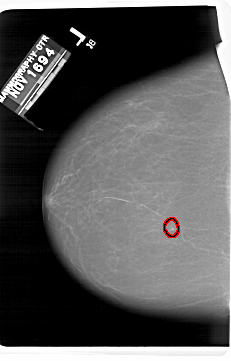

A_1406_1.LEFT_CC

LEFT_CC LINES 6856 PIXELS_PER_LINE 4381 BITS_PER_PIXEL 12 RESOLUTION 43.5 OVERLAY

FILE: A_1406_1.LEFT_CC.OVERLAY

TOTAL_ABNORMALITIES 1

ABNORMALITY 1

LESION_TYPE CALCIFICATION TYPE PUNCTATE DISTRIBUTION CLUSTERED

ASSESSMENT 4

SUBTLETY 4

PATHOLOGY BENIGN

TOTAL_OUTLINES 1